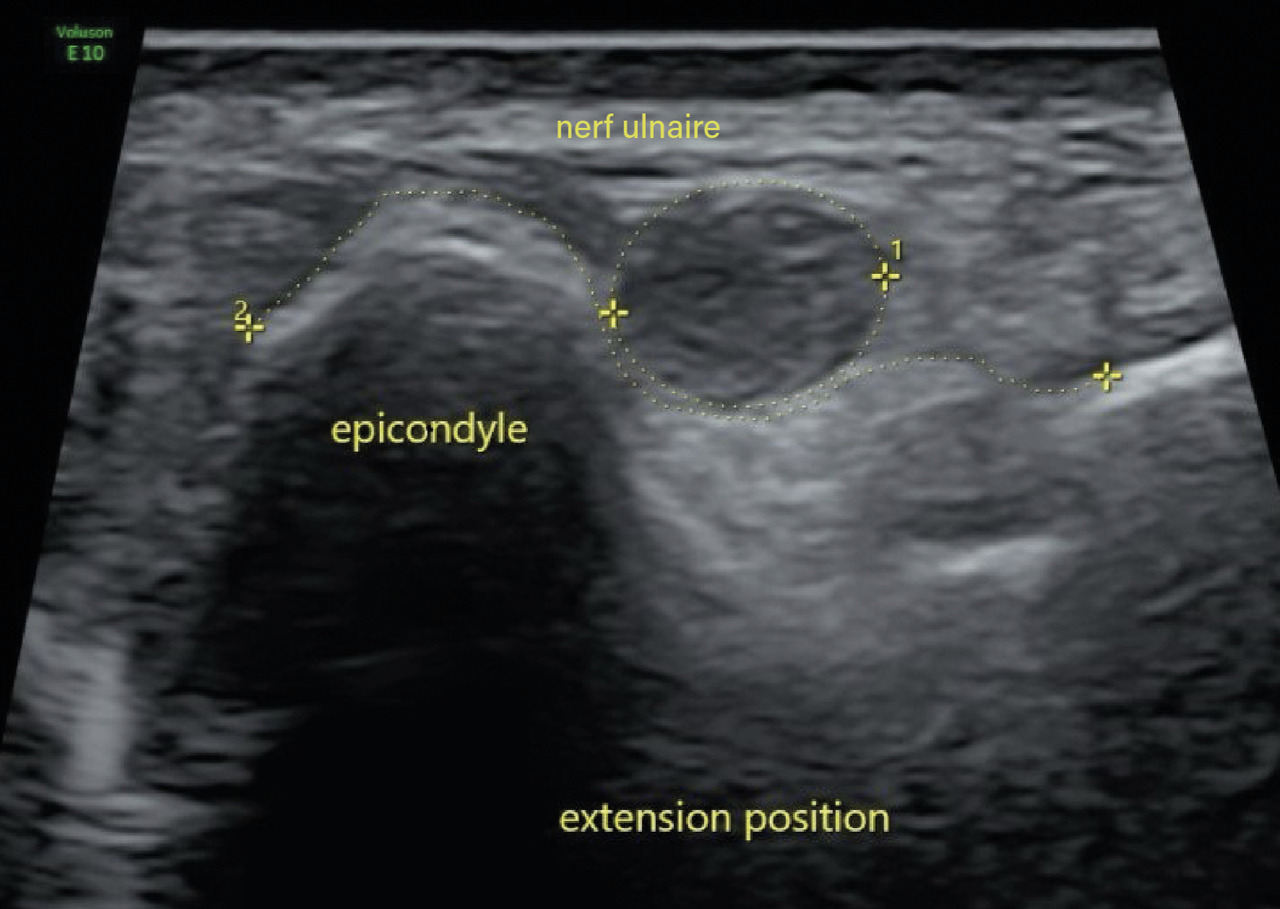

Deux ans après le premier épisode, il reconsulte pour le même motif. Un nouvel EMG révèle un ralentissement de la vitesse de conduction du nerf ulnaire droit au niveau du coude. Une échographie dynamique du coude met en évidence un gonflement fusiforme du nerf ulnaire dans la gouttière cubitale ainsi qu’une luxation du nerf ulnaire au-delà de la tubérosité condylienne lors de la flexion de l’avant-bras sur le bras (fig. 1 et 2). Une transposition cubitale est effectuée (fig. 3) permettant la disparition des symptômes en quelques semaines.

Le diagnostic est posé après réalisation d’une échographie dynamique en flexion et en extension montrant la luxation du nerf ulnaire à la flexion. L’électromyogramme est, quant à lui, moins sensible, pouvant objectiver un bloc de conduction cubital et un ralentissement de la vitesse de conduction au niveau du coude.